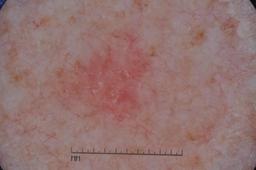

ISIC-DICM-17K (ISIC Dermoscopic Images and Clinical Metadata 17K) is a curated and balanced dataset derived from the International Skin Imaging Collaboration (ISIC) Archive Gallery. It comprises 17,060 dermoscopic images and clinical metadata (8,530 melanoma and 8,530 non-melanoma classes).

For more details, please follow the project’s GitHub repository: https://github.com/mmu-dermatology-research/isic-dicm-17k

This dataset was used in this study and benchmark to explore the effectiveness of multimodal learning for skin lesion classification:

S. Ahammed, X. Cui, W. Lu and M. H. Yap, "Skin Lesion Classification using Dermoscopic Images and Clinical Metadata: Insights from Multimodal Models," 2025 IEEE/CVF Conference on Computer Vision and Pattern Recognition Workshops (CVPRW), Nashville, TN, USA, 2025, pp. 222-230, DOI: 10.1109/CVPRW67362.2025.00027